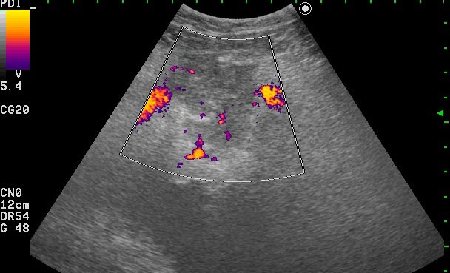

Женщина 42 лет с болями внизу живота, дизурическими явлениями, повышением температуры.

Сонограммы мочевого пузыря

Похоже на опухоль, но по анамнезу я больше склоняюсь к воспалению урахуса!

Согласна с первым постом-возможно нагноение урахуса(и клиника подходит)